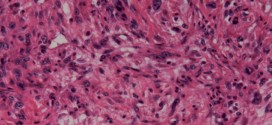

El pseudolinfoma cutáneo. Tumor maligno ó manchas malignas en general y especialmente el formado por células epiteliales o pigmentarias. Los canceres se dividen en dos grandes categorías de carcinoma y sarcoma. La característica básica de la malignidad es una anormalidad de las células, trasmitida a las células hijas, a saber, que se manifiesta por la reducción del control del crecimiento …

La peca melanótica de Hutchinson. Tumor maligno ó manchas malignas en general y especialmente el formado por células epiteliales o pigmentarias. Los canceres se dividen en dos grandes categorías de carcinoma y sarcoma. La característica básica de la malignidad es una anormalidad de las células, trasmitida a las células hijas, a saber, que se manifiesta por la reducción del control …

El carcinosarcoma de próstata. Publicado en: binipatia.com Escrito por: Salvador Gregori Escrivá y IJosh Bush Etiquetas: sustancias súper nutritivas, promover la salud verdadera, arsenal terapéutico alternativo Se trata del tumor maligno más frecuente en los seres humanos. En varones. Durante los primeros años de vida de una persona, las células normales se dividen más rápidamente para permitir el crecimiento. El cuerpo está …